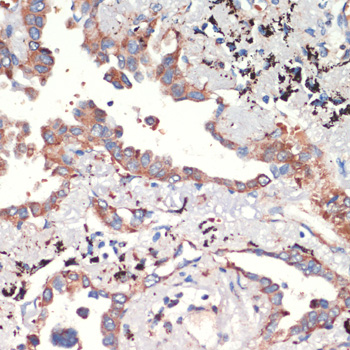

DescriptionAFG3L2 Polyclonal Antibody. Unconjugated. Raised in: Rabbit.

ApplicationWB, IHC, IP